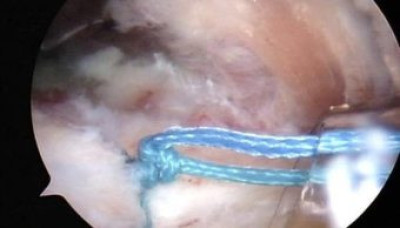

Se esta anudando los hilos de sutura del supraespinoso